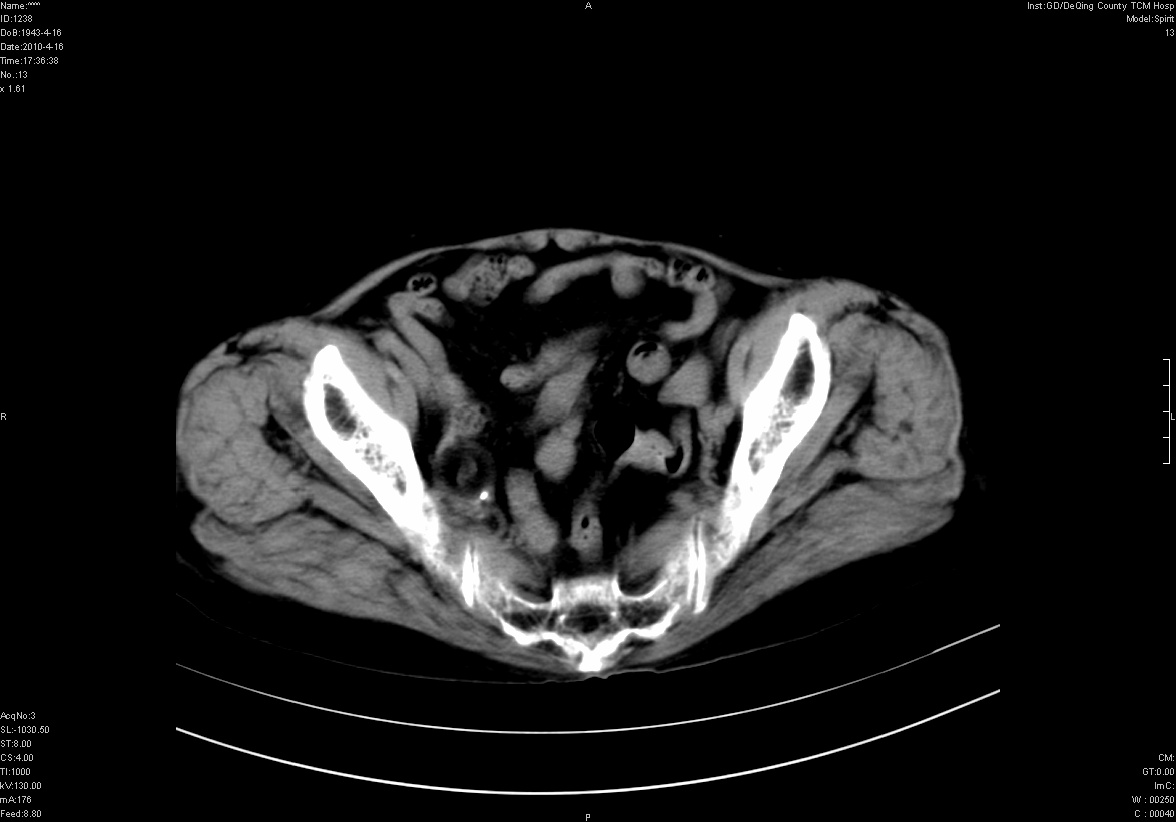

标题: CT25796:女,60岁,腹痛5天,请会诊??? [打印本页]

标题: CT25796:女,60岁,腹痛5天,请会诊???

考虑卵巢畸胎瘤。

支持右侧盆腔畸胎瘤。

畸胎瘤

右侧附件畸胎瘤

考虑右侧卵巢畸胎瘤。

考虑右侧卵巢畸胎瘤

右侧卵巢畸胎瘤可能。